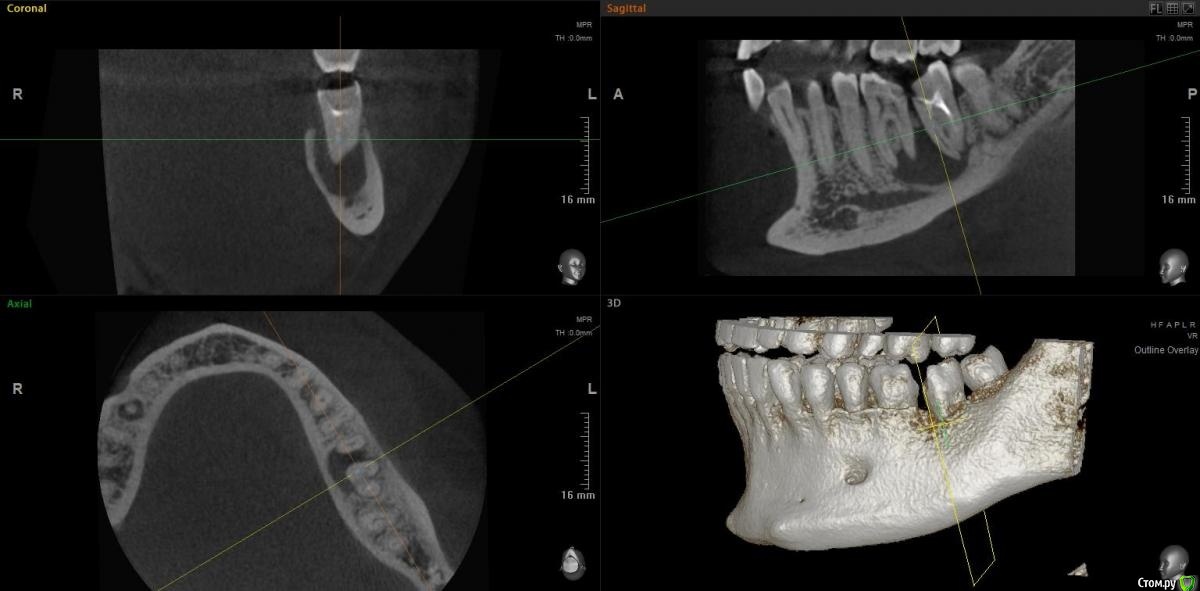

jm3300 Опубликовано 15 ноября, 2020 Поделиться Опубликовано 15 ноября, 2020 Коллеги, можно в данном случае вытянуть консервативно? Ссылка на комментарий

Irouil Опубликовано 15 ноября, 2020 Поделиться Опубликовано 15 ноября, 2020 Тут, похоже, не(только) корневая киста, язычно карман. Вопрос в терапию, наверное, но я скажу - нет 1 Ссылка на комментарий

red_butler Опубликовано 15 ноября, 2020 Поделиться Опубликовано 15 ноября, 2020 Имхо нужно в терапию, по данным срезам не увидел проблем с реэндо 2 Ссылка на комментарий

jm3300 Опубликовано 15 ноября, 2020 Автор Поделиться Опубликовано 15 ноября, 2020 Тут, похоже, не(только) корневая киста, язычно карман. Вопрос в терапию, наверное, но я скажу - нетвозможный карман тоже смущает Ссылка на комментарий

Дмитрий М Опубликовано 15 ноября, 2020 Поделиться Опубликовано 15 ноября, 2020 самого пациента ещё не видел. попросили КТ посмотретьок )) тогда понятноесли только из снимков то 36 пробовать сохранять, эндо и наблюдение а вот 37 больше за удаление был подобный случай, только киста немного меньше была но так же с вовлечением корней 36 и 37 терапевт хотела удалить оба, но решили оставить 36 полечить и наблюдать, а 37(разрушен не подлежал восстановлению) удалил, кисту почистил, ч/з 3 мес имплант. в итоге с 36 все хорошо 1 Ссылка на комментарий